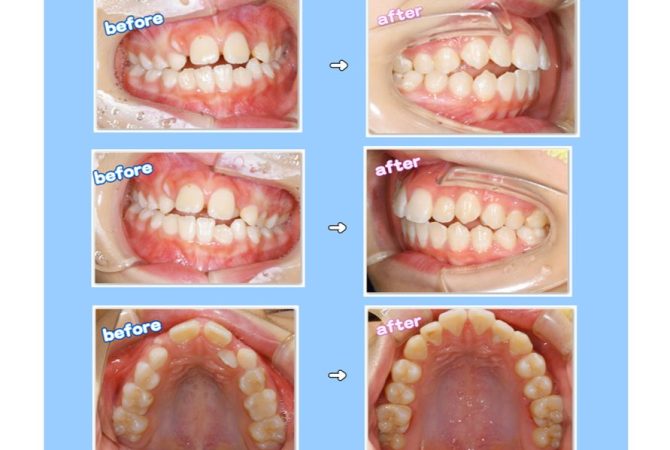

2025.11.15 イベントその他 5歳児健康診査へ行ってきました♪ 詳しく見る 2025.11.14 症例 EMS社エアフローを使用した定期検診症例 詳しく見る 2025.11.12 症例 横向き親知らずの抜歯症例 詳しく見る 2025.10.27 インプラント学び インプラントのための骨造成セミナーを受講 詳しく見る 2025.10.26 イベント院内のこと ハロウィンWeek★キッズイベント開催中 詳しく見る 2025.10.21 学び 博多で歯科麻酔セミナーを受講 詳しく見る 2025.10.19 症例 拡大床と3DLによる小児矯正症例 詳しく見る 2025.10.14 症例 横向き親知らずの抜歯症例 詳しく見る 2025.10.5 治療院内のこと 最新の電動麻酔器を導入♪ 詳しく見る 1 / 29 ページ23…29次へ »